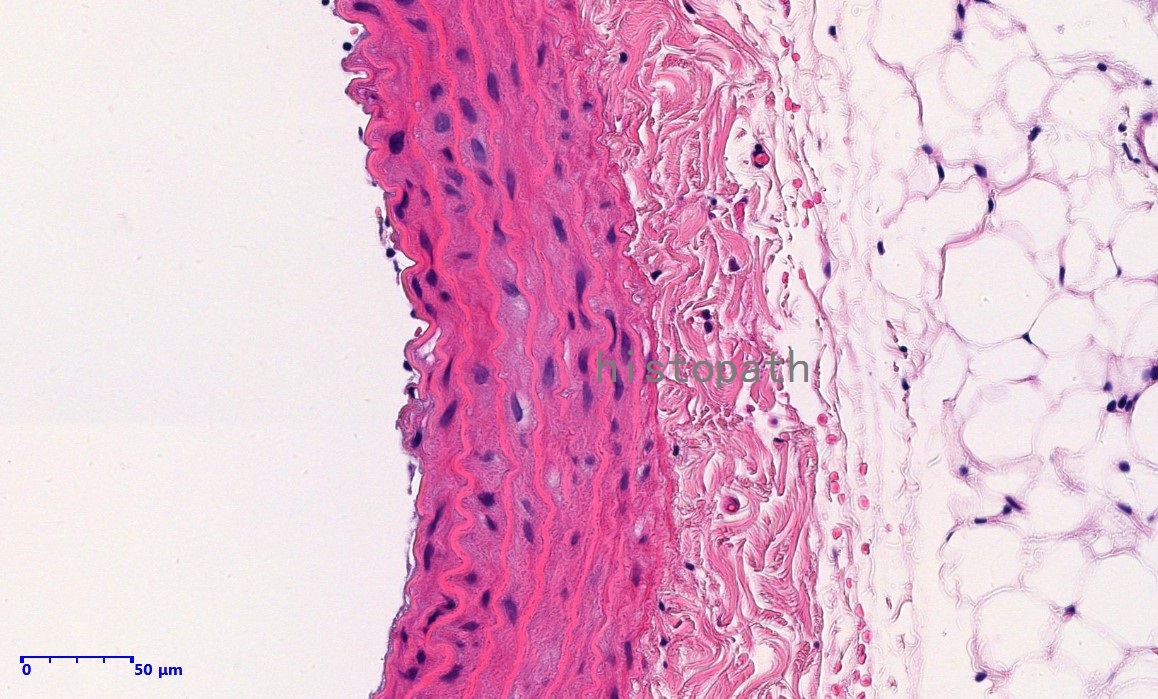

苏木精--伊红染色法(hematoxylin-eosin staining),简称HE染色法,石蜡切片技术里常用的染色法之一。苏木精染液为碱性,主要使细胞核内的染色质与胞质内的核酸着紫蓝色;伊红为酸性染料,主要使细胞质和细胞外基质中的成分着红色。HE染色法使组织学、胚胎学、病理学教学与科研中最基本、使用最广泛的技术方法。

染色结果:

细胞核呈蓝色,细胞质、肌肉、结缔组织、红细胞、嗜曙红颗粒呈不同程度的粉红色。钙盐、软骨基质和各种微生物也可染成蓝色或紫蓝色。核仁呈红色。着色情况不仅与组织或细胞的种类有关,也随其生活周期及病理变化而改变。质量优良的HE染色切片样本,细胞核与细胞质蓝红对比明显,胞核鲜明,核膜及核染色质颗粒均清晰可见。